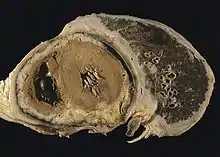

The mesothelium consists of a single layer of flattened to cuboidal cells forming the epithelial lining of the serous cavities of the body including the peritoneal, pericardial and pleural cavities.[51] Deposition of asbestos fibers in the parenchyma of the lung may result in the penetration of the visceral pleura from where the fiber can then be carried to the pleural surface, thus leading to the development of malignant mesothelial plaques. The processes leading to the development of peritoneal mesothelioma remain unresolved, although it has been proposed that asbestos fibers from the lung are transported to the abdomen and associated organs via the lymphatic system.[52] Additionally, asbestos fibers may be deposited in the gut after ingestion of sputum contaminated with asbestos fibers.

Pleural contamination with asbestos or other mineral fibers has been shown to cause cancer. Long thin asbestos fibers (blue asbestos, amphibole fibers) are more potent carcinogens than "feathery fibers" (chrysotile or white asbestos fibers).[28] However, there is now evidence that smaller particles may be more dangerous than the larger fibers. They remain suspended in the air where they can be inhaled, and may penetrate more easily and deeper into the lungs. "We probably will find out a lot more about the health aspects of asbestos from [the World Trade Center attack], unfortunately," said Dr. Alan Fein, chief of pulmonary and critical-care medicine at North Shore-Long Island Jewish Health System.[53]

Mesothelioma development in rats has been demonstrated following intra-pleural inoculation of phosphorylated chrysotile fibers. It has been suggested that in humans, transport of fibers to the pleura is critical to the pathogenesis of mesothelioma. This is supported by the observed recruitment of significant numbers of macrophages and other cells of the immune system to localized lesions of accumulated asbestos fibers in the pleural and peritoneal cavities of rats. These lesions continued to attract and accumulate macrophages as the disease progressed, and cellular changes within the lesion culminated in a morphologically malignant tumor.